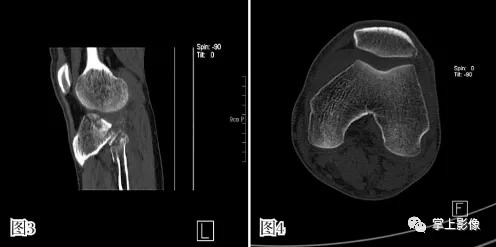

图1 、2为同一患者胫骨平台骨折合并积脂血症不同界面的 CT 表现,液平上方为脂肪,下方为关节内出血,可见单液-液平面征。图 3 为髌上囊积脂血征,胫骨平台骨折合并腓骨小头骨折。图 4 为 1 例隐匿性骨折患者,男,48 岁,车祸外伤,左膝关节活动受限,普通 X 线检查提示髌上囊内密度升高,常规平扫见脂液平面,经薄层重建充分显示左髌骨外侧缘撕脱骨折

- 而双液-液平面的形成则于进入关节腔隙内的血液静置后,血清与血细胞的分层有关,血液在静置 3 小时后,血清和血细胞即可发生分离,形成不同的平面分层,而小部分患者在关节发生创伤后,可能因长时间无法移动而导致双液-液平面的形成,但是这种情况相对少见,多数患者在接受关节检查前,受各种外源性因素的影响,无法保持长时间不移动的情况,以单液-液平面现象为主要特征